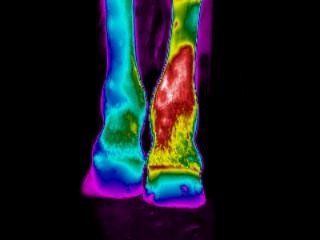

Sofern bei deinem Pferd innerhalb der letzten 3 Monate beispielsweise ein Sehnenschaden, Knochenbruch diagnostiziert oder eine OP vorgenommen wurde, werden bei der OP-/Verletzungskontrolle Thermogramme von dem/den betreffenden Bereich(en) angefertigt, um den Heilungsverlauf optimal beobachten zu können.

Linkes Knie 2 Tage, 4 Wochen und 8 Wochen nach einer Arthroskopie: